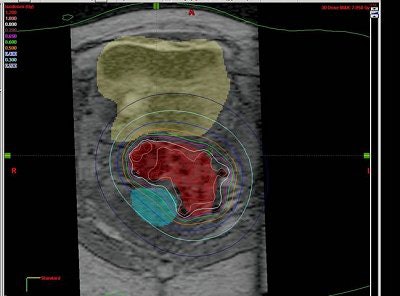

![]() |

| Tumor volume on MRI (above) and CT (below). Images courtesy of Dr. Akila Viswanathan. |

Based on the DVH analysis -- done with CT volumes because that is the standard, Viswanathan added -- the median tumor volume was 80 cc. The median V150 was 60%, the median V90 was 82%, and the median V95 was 90%.

"For bladder and rectal DVHs, we saw that the median bladder total volume was 68 cc. We then calculated the 2-cc and 5-cc percent-of-treatment to the bladder volume and it was 80% and 70%, respectively," she said. "The median rectal volume was contoured for 55 cc and we saw that the 2-cc and 5-cc volumes were 90% and 80% of our prescription."

"We concluded that MR-guided interstitial brachytherapy is feasible. It does prevent the insertion into the bladder and rectum. It does allow conformal treatment planning and accurate delineation of the tumor, bladder, and rectum," she stated.